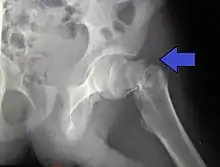

A case demonstrating a possible order of imaging in initially subtle findings:

X-ray showing a suspected compressive subcapital fracture as a radiodense line

CT scan shows the same, atypical for a fracture since the cortex is coherent

T1-weighted, turbo spin echo, MRI confirms a fracture, as the surrounding bone marrow has low signal from edema.